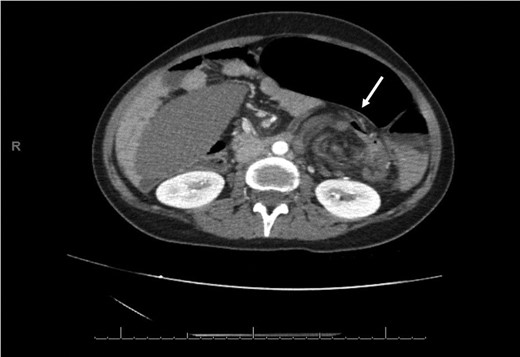

An axial CT of the upper level of the abdomen shows a corkscrew-like soft tissue density (white arrow) indicating twisted splenic vessels surrounded by peritoneal ligaments and fats forming a whirly appearance with alterative lucent and dense bands (a whirl sign), is a pathognomonic CT findings of torsion.